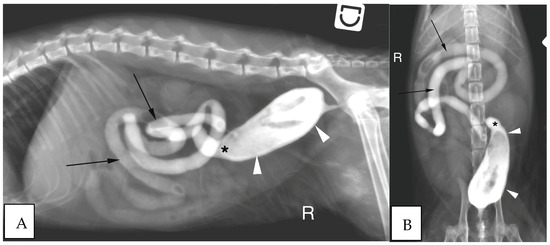

3.2.4. Endoscopic Findings